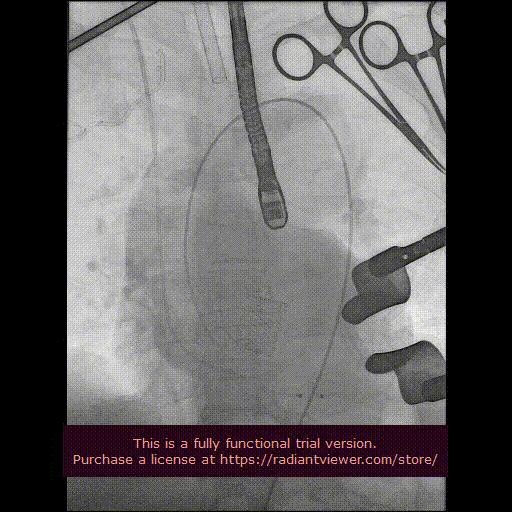

用经胸超声心动图确定心尖位置,并做好标记。常规肝素化,按照心尖标记,行第5、6 肋间左胸前外侧小切口,充分暴露心尖后将心包切开并悬吊,用3-0 Prolene 线加毛毡片完成荷包缝合。经股动脉植入6Fr鞘管,并插入猪尾造影导管至主动脉根部,造影确定主动脉瓣瓣环水平及两侧冠状动脉开口。

经心尖途径置入 J-Valve 瓣膜输送系统,在升主动脉部打开定位件,调整角度,轻轻向后牵拉输送器使定位件进入主动脉窦内。联合主动脉根部造影和食管超声观看定位件是否定位于窦底,形态随着心脏跳动而自然摆动即可。下降瓣膜至主动脉瓣环内,在主动脉瓣口释放瓣膜支架,此过程无需快速起搏。瓣膜成功释放后移除瓣膜输送系统。行主动脉根部造影及经食管超声检查,对瓣膜功能、位置情况进行术后即刻评估。确认位置良好、功能正常后,移除导丝及输送系统,并收紧心尖荷包缝线打结固定。

最后再次血管造影确认介入瓣膜位置稳定,活动良好,无瓣周漏,冠状动脉开口无阻塞。

造影显示主动脉窦部

从心尖置入输送系统

定位件入窦

瓣膜降至瓣环平面

释放瓣膜

造影确认瓣膜位置

撤出输送系统

造影确认植入效果